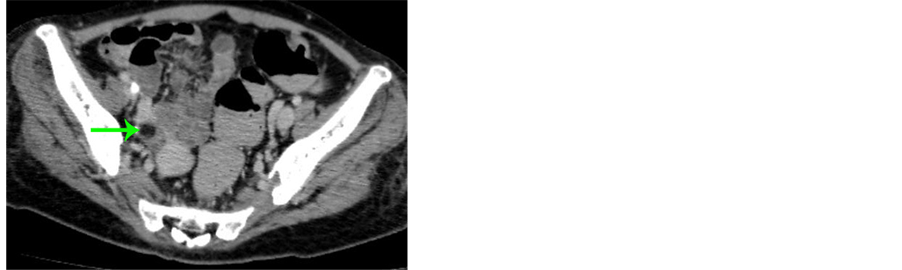

Nmda receptor encephalitis is a rare disease first described in 2007. Early symptoms may include fever, headache, and feeling tired. The patient was transferred to the neurology ward, where an endovaginal ultrasound showed an ovarian teratoma in her right ovary.

We report on the surprising diagnostic quest in a young black woman with. The patient was transferred to the neurology ward, where an endovaginal ultrasound showed an ovarian teratoma in her right ovary. Our objectives were to analyze prevalence and outcome of this association, and increase awareness over this pathology.

1,2 up to 50% of patients have tumors, mainly ovarian teratomas. One of them is ovarian teratoma, which. Subsequent excision confirmed a stage 1a g1 immature ovarian teratoma on histopathological examination.